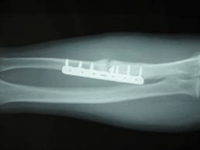

ידוע לנו כי שברים טופלו לאורך ההיסטוריה בעזרת קיבוע, מתיחה, קטיעה וכן קיבוע פנימי. קיבוע על ידי ייצוק, רצועות תומכות, או קיבוע משותף מעל ומתחת לשבר שימש לטיפול בשברים בעיקר בעצמות הארוכות יותר, למעט עצם הירך, אשר המתיחה היתה עמוד התווך של הטיפול בה. בעבר, שברים פתוחים ופציעות בליסטיות עם שברים בעצמות הארוכות לא היו ניתנים לטיפול כשברים רגילים בגלל הפגיעה ברקמות הרכות והקושי במניעת קרישי דם, ולכן הם בדרך כלל טופלו על ידי קטיעה, במיוחד במהלך מלחמת האזרחים בארה"ב (4) . הרעיון של קיבוע פנימי מתוארך לאמצע 1800 (ליסטר הציג קיבוע פנימי (ORIF), של פיקת ברך שבורה כבר ב- 1860). השימוש בצלחות, ברגים וחוטים תועד לראשונה בשנת 1880 ו 1890. בתחילת הדרך, קיבעון כירורגי היה מסובך בגלל מכשולים רבים, כגון: זיהום, שתלים גרועים וטכניקות לא מתאימות, אלרגיה למתכות ובעיקר הבנה מוגבלת של הביולוגיה ומכאניקה של ריפוי שברים. במהלך 1950, החלו דניס ומולר להגדיר את העקרונות והטכניקות של קיבוע פנימי. במהלך 40 השנים האחרונות, ההתקדמות במדע הביולוגיה ומדע המכאניקה הובילו עדכון וחידוש של תיאוריות וטכניקות קיבוע (5).

ייצוב מוחלט של שבר על ידי קיבוע פנימי, מוביל לשינוי ביולוגי של ריפוי ע"י צמצום המתח שנוצר באזור רקמת הריפוי בסמוך לשברים (1).

חוטים מנוצלים לקיבוע זמני, לפני קיבוע מוחלט עם מכשיר חזק, ההתנגדות לכיפוף עם החוטים הוא מינימאלי. החוטים משמשים לעתים קרובות כמו תפרים, על מנת "לתפור" את העצמות בחזרה יחד (4).

הרכב העצמות וצפיפות העצם, הוא הנתון הקובע העיקרי בקיבעון הבורג (6).